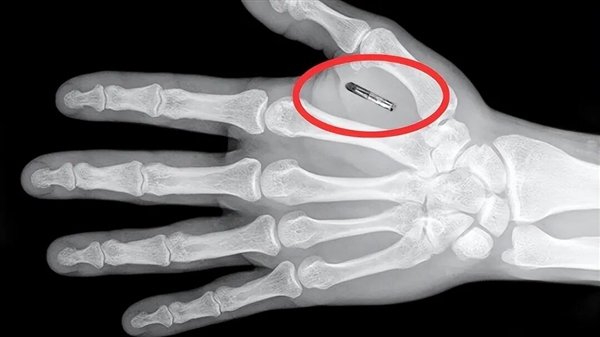

男子叫王子腾(Zi Teng Wang),是一名魔术师,据他介绍,几年前,为了提升表演效果,他在自己的手掌虎口位置植入了一枚RFID(射频识别)芯片。

比较常见的芯片一般只有米粒大小,植入费用一般在150-400美元之间(有的公司需要每年支付数据访问费用),大多在手上,它的功能也很多。